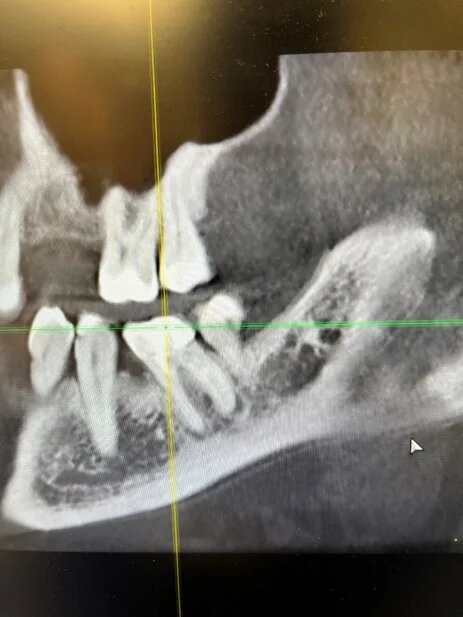

У него было воспаление на корне зуба. Сам зуб скрывался под пломбой — та уже изрядно покололась.

Когда мы её убрали, картина стала яснее:

-стенки зуба — розоватого оттенка;

-дно — тёмно‑коричневое;

-ткани корня-твердые

Мы обсудили с пациентом все нюансы и приступили к лечению. Но тут у многих закономерно возник вопрос: что вообще происходило с этим зубом? Почему он такого цвета? И почему не гнилой?

Ответ прост: виной всему — устаревший резорцин‑формалиновый метод пломбирования каналов. Да‑да, тот самый, который до сих пор кое‑где применяют.

2 ) Плохая герметичность. Смесь мумифицирует нерв, но плохо закупоривает верхушку корня. В процессе затвердевания смесь дает усадку и образовывает пустоты. Поэтому инфекция часто выживает, проникает за верхушку и образовывает кисты.

7 ) Плохая эстетика. Зуб окрашивается в розовато-коричневатый оттенок. На задних зубах это не так заметно, но передние выглядят… своеобразно. Резорцин плотно въедается в ткани, даже отбеливание не всегда работает. Часто прибегают к винирам или коронкам.